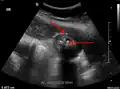

Right upper quadrant abdominal ultrasound is most commonly used to diagnose cholecystitis.[1][26][27] Ultrasound findings suggestive of acute cholecystitis include gallstones, pericholecystic fluid (fluid surrounding the gallbladder), gallbladder wall thickening (wall thickness over 3 mm),[28] dilation of the bile duct, and sonographic Murphy's sign.[13] Given its higher sensitivity, hepatic iminodiacetic acid (HIDA) scan can be used if ultrasound is not diagnostic.[13][14] CT scan may also be used if complications such as perforation or gangrene are suspected.[14]

Abdominal ultrasonography showing gallstones, wall thickening and fluid around the gall bladder